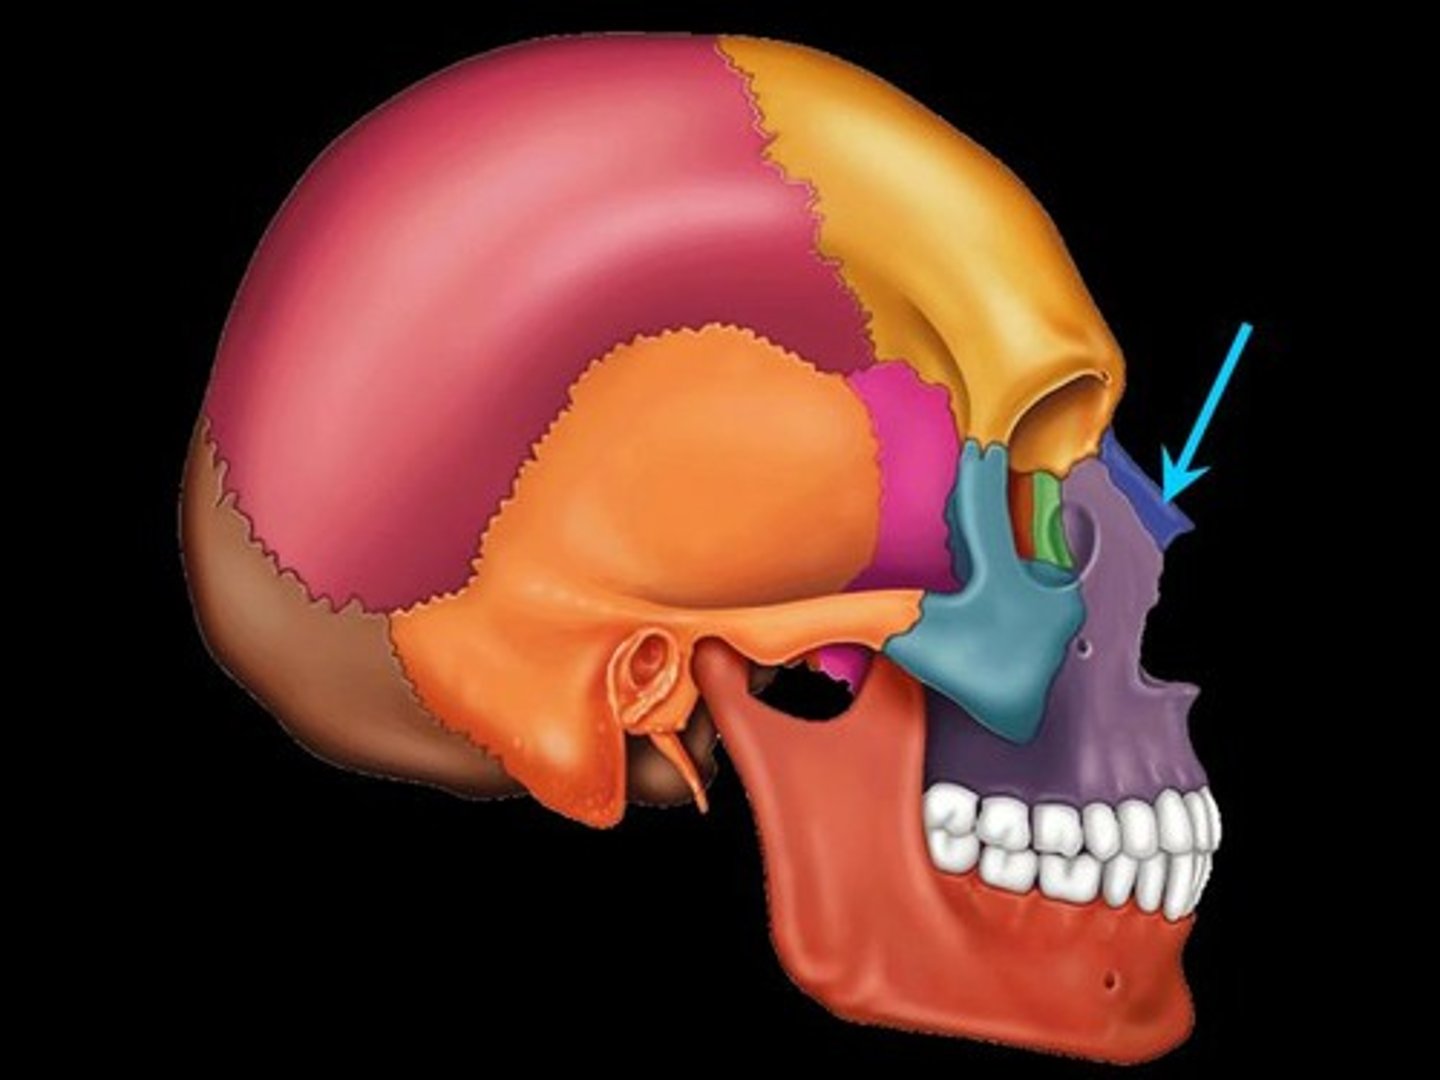

Orbital

Eye cavity